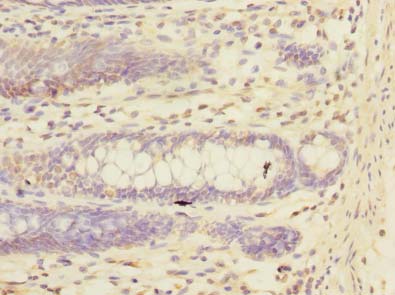

ApplicationELISA, WB, IHC; Recommended dilution: WB:1:500-1:2000, IHC:1:20-1:200